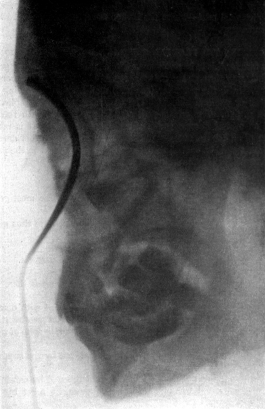

| 279. | Upper Bronchoscopy with the Patient in the Dorsal Position | 564 |

| 280. | Lower Bronchoscopy with the Patient in the Dorsal Position | 565 |